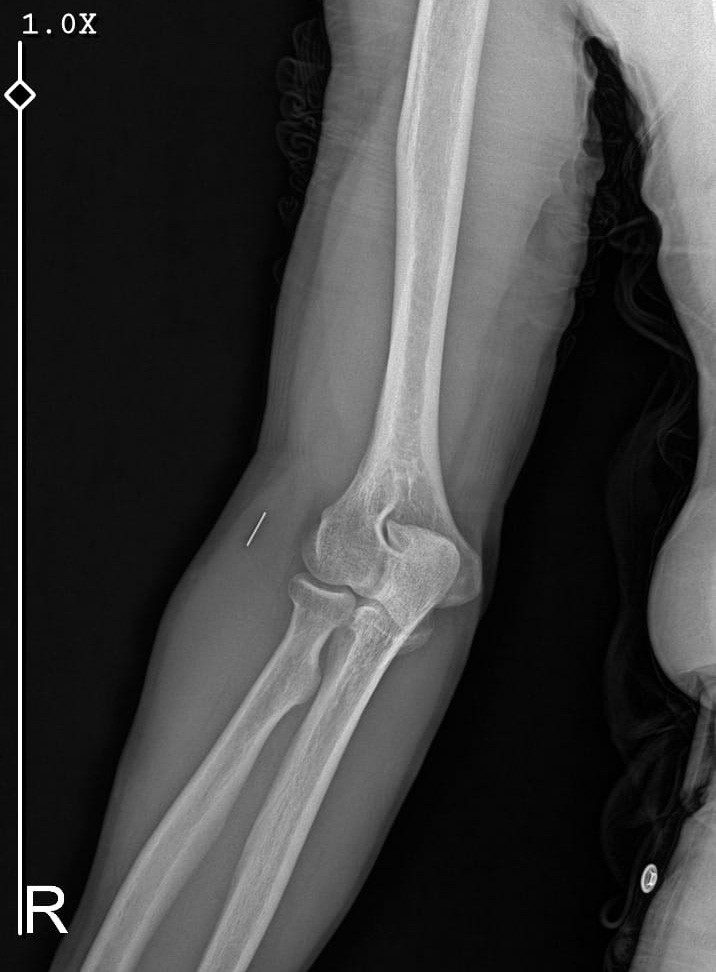

Öte yandan, ameliyatların ardından ağrıları devam eden Güleryüz’ün kolunda metal parça bulunduğu ve bu parçanın parmak bölgesinden dirseğe doğru ilerlediği öne sürüldü. Ayrıca, fabrikada temizlik personeli olarak çalışan Nurettin Güleryüz’ün hastane sürecinde işten çıkarıldığı da öğrenildi.

"Doktorlara bileğime doğru ağrılarım olduğunu sürekli ifade etmeme rağmen beni dinlemediler. Sonradan kolumda metal kaldığını öğrendik. Bunun ihmal olduğunu düşünüyoruz. Çünkü kola metal nasıl girebilir? Ben 9 aydır çalışamıyorum. Kalp rahatsızlığım sebebiyle yüzde 46 engelliyken şu anda yüzde 75 engelli durumuna düştüm. Erken emeklilik dilekçesi verdim ancak henüz sonuç gelmedi. Bu konuda çok mağdurum. Yetkililerin bunu duymasını istiyorum. Savcılığa suç duyurusunda bulunduk. Yaklaşık 9 aydır henüz soruşturma izni gelmedi. Süreci bekliyoruz, henüz dava açılmış değil. Kolumda bırakılan metal ilerliyor. Pazartesi günü bunun için de operasyon geçireceğim. Çıkarılıp çıkarılamayacağı net değil. Elimde titremelerim var, çalışamıyorum ve işveren tarafından işten çıkarıldım. Yetkililerden destek ve konunun incelenmesini talep ediyorum."